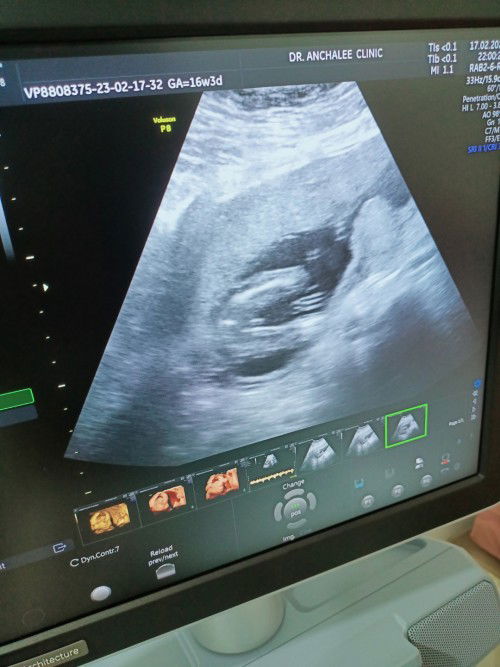

ดูให้หน่อยค่ะ ชายหรือหญิง หมอบอก50/50 มีโอกาสเป็นหญิงไหมค้ะ#ขอบคุณล่วงหน้านะคะ

แม่ๆว่าเพศหญิงหรือชาย หมอบอก50 50 มีโอกาสเป่นหญิงไหม ##ขอบคุณล่วงหน้านะคะ

แม่ๆช่วยดูหน่อย ว่าเพศชายหรือเพศหญิง หมอบอก 50/50 มีสิทธิ์เป่นหญิงไหมค้ะ หมอบอกบางมุมเหมือนหญิง บางมุมเหมือนชาย # ##ขอบคุณสำหรับคำตอบค่ะ